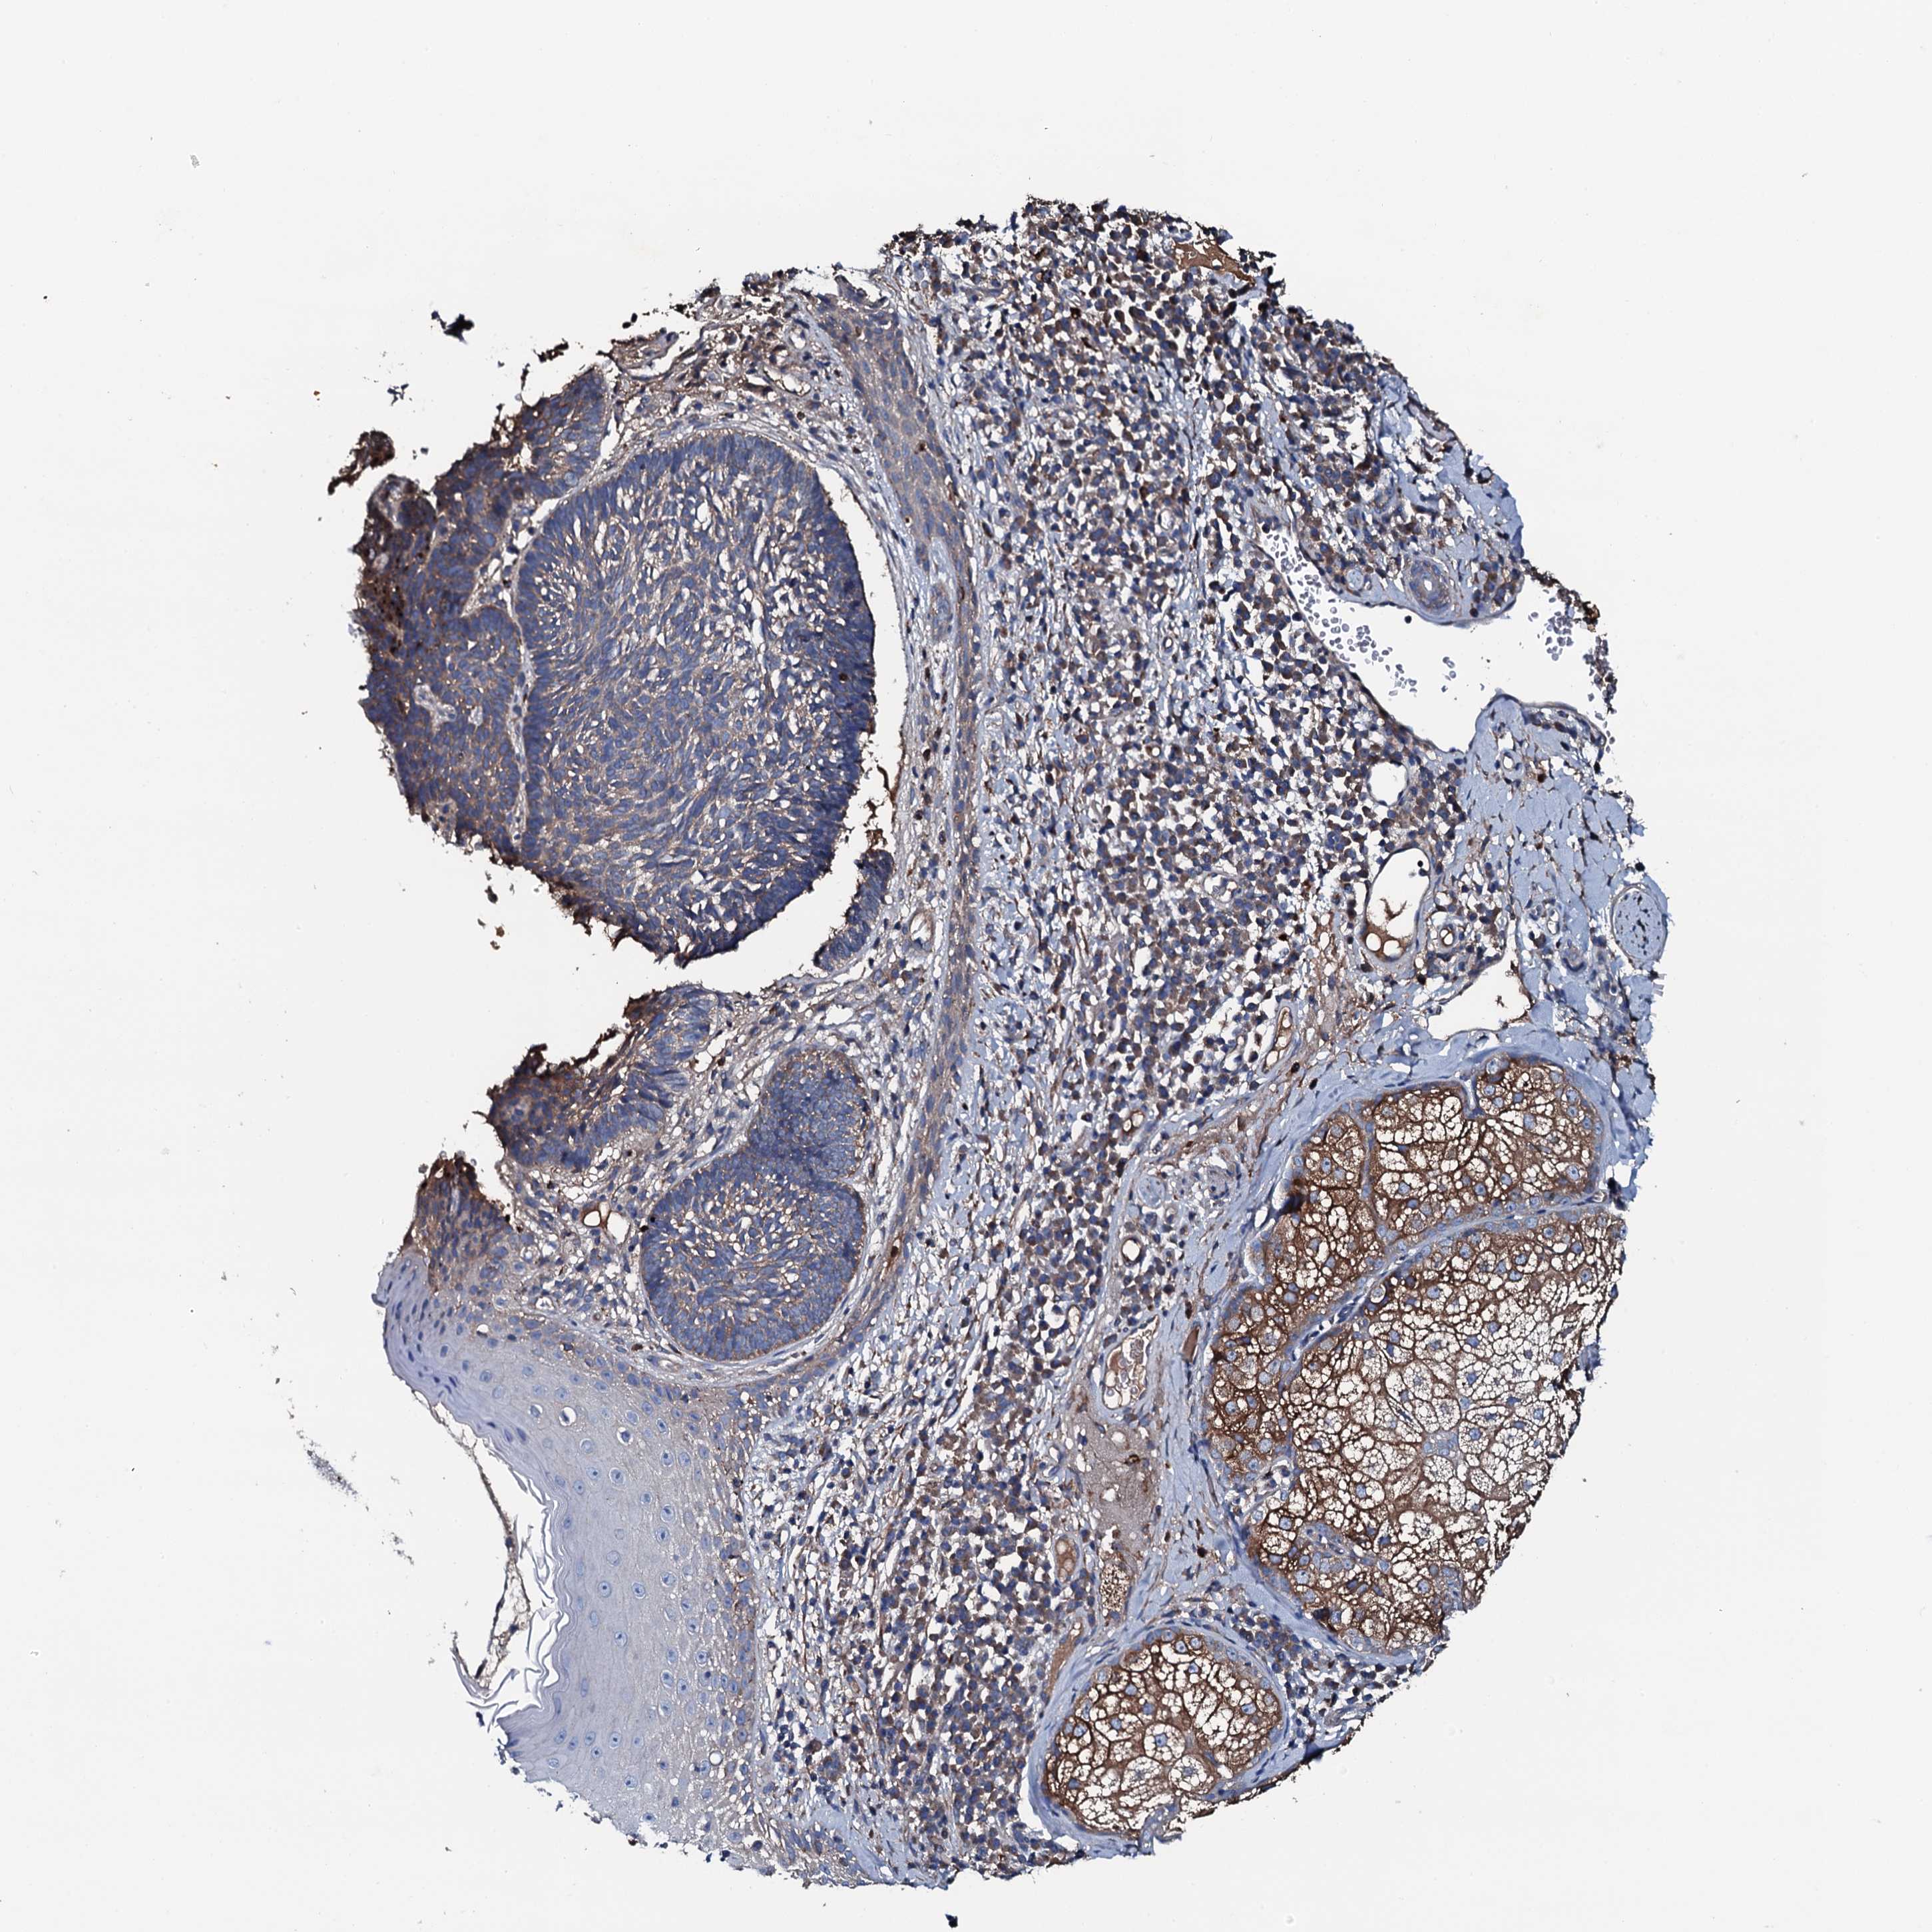

CANCER SKIN CANCER Show tissue menu

Basal cell and squamous cell cancer

SKIN CANCER - Protein expressioni

A mouse-over function shows sample information and annotation data. Click on an image to view it in a full screen mode. Samples can be filtered based on level of antibody staining by selecting one or several of the following categories: high, medium, low and not detected. The assay and annotation is described here.

Each image is clickable and will lead to virtual microscopy that enables deeper exploration of all samples and also displays staining intensity scores, fraction scores and subcellular localization as well as patient and tissue information for each sample.

Antibody HPA020873

Antibody HPA040413

Basal cell carcinoma

Squamous cell carcinoma, NOS

Squamous cell carcinoma, metastatic, NOS